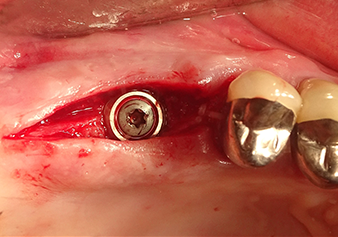

The Schneiderian membrane is stretched 1.5-2 mm above the bony access

Fig.4: Intermediate check: The bone height above the maxillary sinus floor is approx. 4 mm palatal and buccal; the Schneiderian membrane is stretched 1.5-2 mm above the bony access.